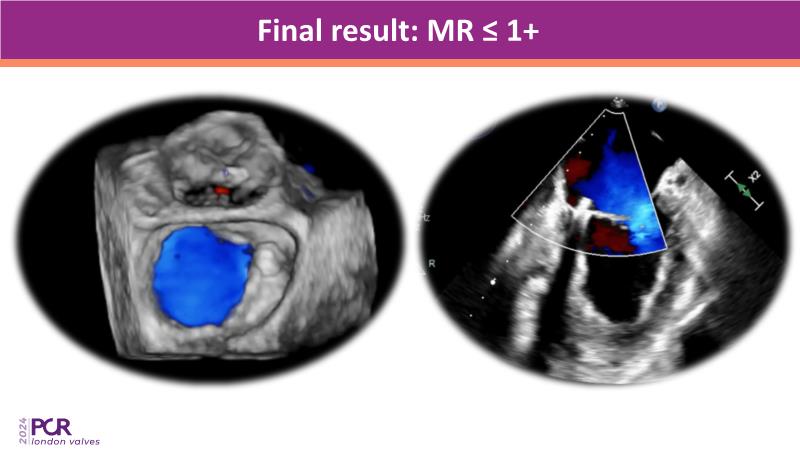

Explore the differentiating features of the PASCAL Precision system for the treatment of patients with mitral regurgitation through simulation and case-based learning.

• To understand when and how the PASCAL implants may be used for successful treatment of mitral regurgitation in a broad range of anatomical situations

• To learn more about the key features of the PASCAL Precision system that facilitate the mitral TEER procedure and contribute to successful clinical outcomes